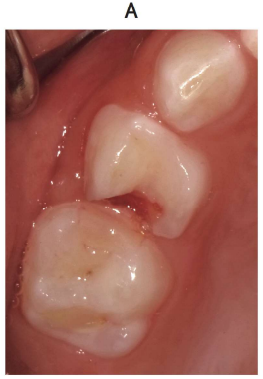

4 歳の女児。上顎右側乳臼歯部の激しい疼痛を主訴として来院した。 3 か月前に上顎右側D のコンポジットレジンの脱離に気付いていたが、症状がないためそのままにしていたところ、昨晩から痛みが続いているという。上顎右側のD に打診痛を認める。初診時の口腔内写真(別冊No. 21A)とエックス線画像(別冊No. 21B)を別に示す。

解答:c

解説:

根尖病巣はなさそう。

打診痛あり、痛みもある⇒歯髄まだ生きてそう。後継歯の歯冠もしっかりできているので⇒抜髄

抜歯してしまうと、4がはえてくるのはまだ先なのでスペースが空いてしまうので残しておくのがよい。